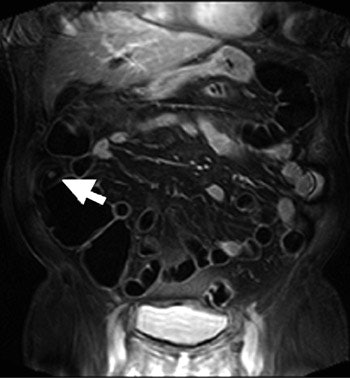

![]() |

| Seventy-three-year-old man with history of polypectomy. Coronal source image of 3D gradient-echo dataset shows small polyp in ascending colon (arrow) (AJR 2005; 184:598-611). |